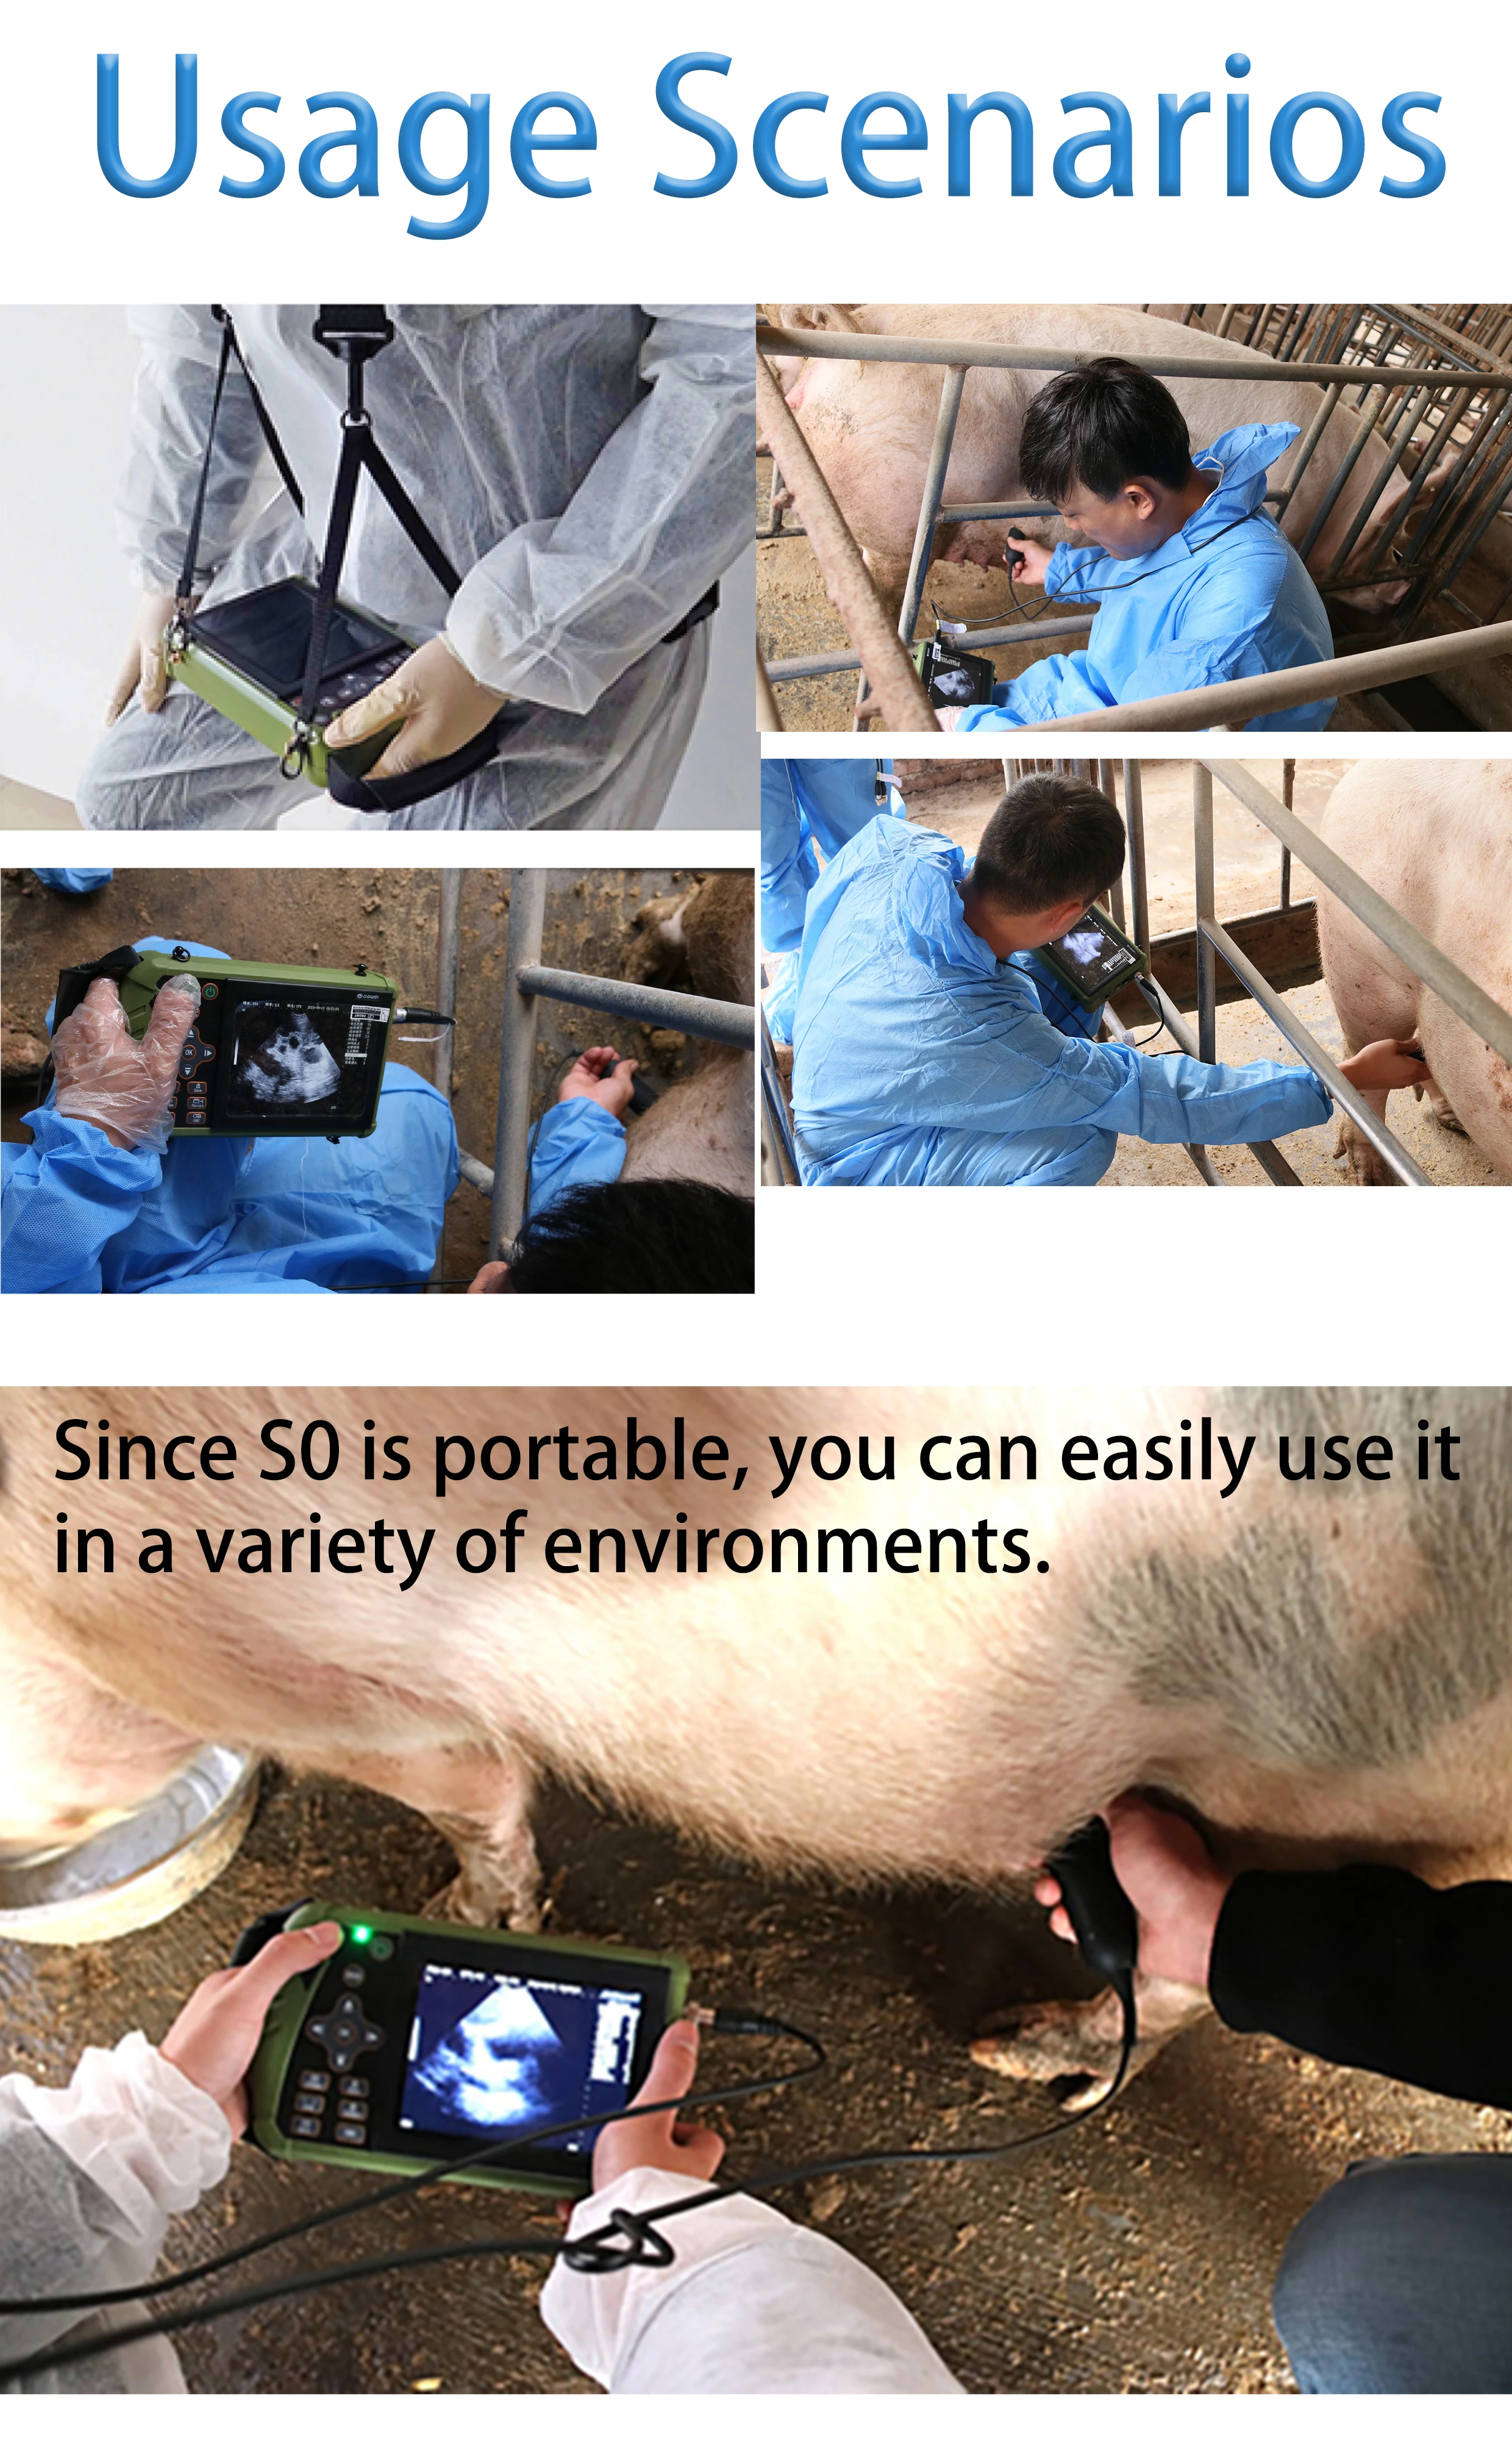

This machine can be used for both humans and animals: